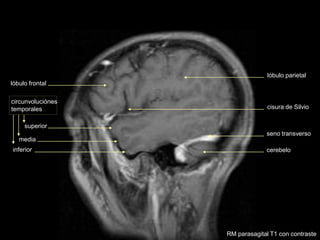

cisura de Silvio

superior

media

inferior

circunvoluciónes

temporales

cerebelo

seno transverso

lóbulo parietal

lóbulo frontal

RM parasagital T1 con contraste